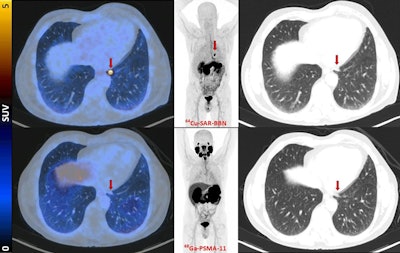

Fused PET/CT, maximum-intensity projection PET, and lung-windowed CT images (from left to right) from Cu-64 SAR-BBN (top row) and Ga-68 PSMA-11 (bottom row) PET/CT study of patient demonstrating left subpleural lesion (arrows, SUVmax of 10 at 1 hour) that showed Cu-64 SAR-BBN uptake but no Ga-68 PSMA-11 uptake. PSA was 1.84 ng/mL at time of imaging. This patient underwent lobectomy, with histopathology demonstrating metastatic prostate cancer.Image courtesy of the Journal of Nuclear Medicine